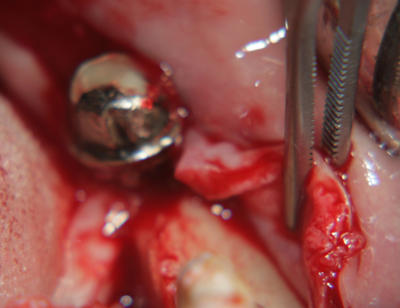

На тази снимка се вижда зъбната алвеола след изваждането на зъба. Формата на алвеолата е изключително подходяща за имедиатно имплантиране - кръгла, без междукоренови прегради, с добре запазени костни стени. Вестибуларно се вижда костен израстък, който бързо би се лизирал ако не се постави имплантат - всяка структура в организма, която не е подложена на функционално натоварване, започва да атрофира много бързо. Поради това всички автори в световната литература са единодушни за един факт: имедиатното имплантиране предпазва от костна загуба поради липсата на време за афункционална атрофия. В този ред на мисли описаният случай на имедиатно имплантиране има много по-добра прогноза, отколкото ако се изчака оздравяването на екстракционната рана.